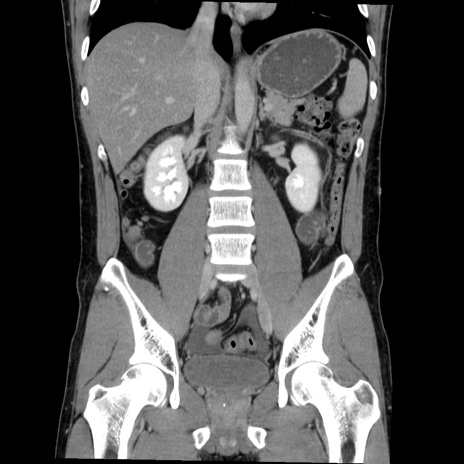

症例36(冠状断像)

【症例】20歳代 男性

【主訴】心窩部痛

【現病歴】今朝より上腹部痛あり。一旦軽快していたが再度出現したため救急要請。昨日夕に白身の魚を含む刺身を食べた。

【身体所見】BP 136/89mmHg、HR 74/min、BT 37.0℃、腹部:膨満、軟、心窩部に圧痛あり。反跳痛なし、筋性防御なし、腸雑音やや亢進あり。

【データ】WBC 17700、CRP 0.48